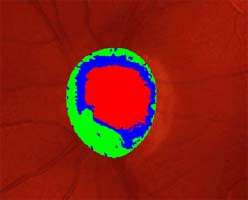

Očekávali byste protažení exkavace k hornímu pólu terče, jak nám ukazuje tento snímek z tomografu HRT II.

exkavace levé oko

Na kterém oku je exkavace větší, na pravém nebo na levém? Podle pohledu na fotografie jistě na levém.

Co je příčinou toho, že při pohledu na snímky hodnotíme rozsah exkavace nesprávně? Je to skutečnost, že i růžová oblast neuroretinálního lemu může být již prohloubená, což vídáme zvláště na počátku rozvoje glaukomové neuropathie.

A jak se můžeme vyhnout záměně okrsku bledší barvy za skutečnou exkavaci? Tím, že budeme mít na paměti, že exkavace může být větší než nablednutí. Také zařazení zeleného filtru na pomůže snížit nežádoucí barevný kontrast.